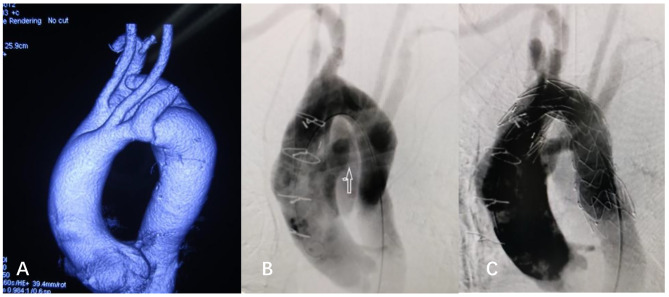

Case 2

, a 41 years old male patient was transferred to hospital in June 2019 due to “sudden chest and back pain for one day”. He had progressive dysphagia with hoarseness in recent months. Aortic CTA indicated that (Fig. 1.B): DAA, and dissected aneurysm formed in the descending aortic arch. Both left and right arches gave rise a common carotid artery proximally and a subclavian artery distally. The diameter of the anterior arch was larger than posterior arch (1.8 cm vs. 1.3 cm).

During DHCA, a covered stent (MicroPort 26 mm*120mm) was placed in the true lumen of the descending aorta. LSA, LCA and RCA were reconstructed using vascular graft with branches (Terumo 24 mm). Due to its deep location, it was hard to expose and reconstruct RSA (Fig. 1.C). The surgical time of operation, cardiopulmonary bypass, and aortic cross clamp were 7 h, 115 min, and 40 min respectively. During three-year follow-up time, the symptoms of dysphagia and hoarseness were obviously improved.

Fig. 2.

Combined operation for aortic arch dissection with DAA

A, showed DAA with the right dominant arch and dissection at the descending arch

B, arrow indicated the severed left arch and the reconstructed LSA.

C, showed a membrane stent sealed the breach of descending arch